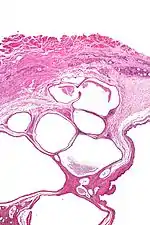

Micrograph of a cystic tumour of the atrioventricular nodal region. H&E stain.

Cystic tumours of the atrioventricular nodal region, true to their name, have cystic spaces, which are lined by a single layer of histomorphologically benign epithelial cells. The appearance is similar to that of lymphangioma and this is a name that has been used for this tumour.[1]